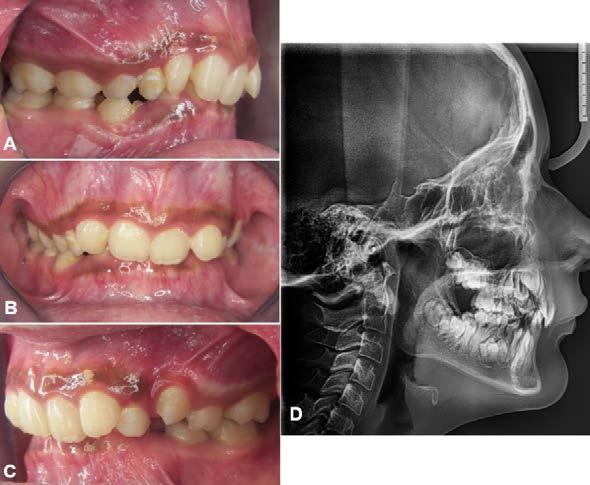

Caso clínico

Paciente masculino de 18 años de edad con motivo de consulta: “Quiero arreglar toda mi dentadura”, diagnosticado con clase II esquelética, biotipo facial mesofacial, perfil convexo, clase II canina y molar bilateral, línea media superior coincidente con la facial, línea media inferior desviada a la izquierda 2 mm, overjet aumentadado con 9 mm y overbite disminuido a 17%.

Estudios intraorales de inicio

En la fotografía lateral derecha (Figura 4), de frente e izquierda se ve la clase II canina y molar bilateral, curva de Spee acentuada y laterales microdónticos. La línea media dental inferior está desviada a la izquierda 2 mm. En las oclusales superior e inferior, el apiñamiento leve superior e infierior, laterales superiores

microdónticos y formas de arco cuadradas (Figura 5).

Figura 4. Intraoral derecha, frente, izquierda.